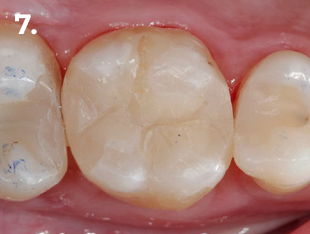

Fig. 7 Imagen Clínica final

Paciente que acude a consulta refiriendo molestias en la zona del primer cuadrante. La exploración clínica y radiográfica reveló la presencia de una caries profunda distal, estableciéndose el diagnóstico pulpar de pulpitis reversible. Con el objetivo de lograr un adecuado punto de contacto tanto mesial como distal, se procedió a la eliminación completa de la restauración existente. El procedimiento se realizó bajo aislamiento absoluto, utilizando para el encofrado el sistema de matrices seccionales HALO. En la imagen clínica y radiográfica final se observan perfiles de emergencia bien conformados, convexos, así como puntos de contacto adecuados.